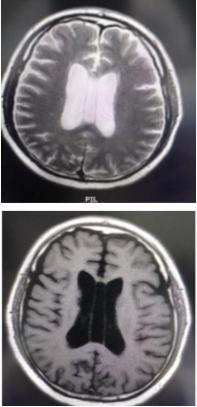

透明隔腔≥3mm,直径<10mm,描述可见透明隔腔增宽,透明隔的两壁呈前后平行排列,边界清晰,或内凹,对周围组织无压迫,为正常生理变异,临床无症状。透明隔腔≥10mm,描述可见透明隔腔明显增宽。

透明隔囊肿

若两侧侧脑室间的含液结构的两侧壁向两侧弯曲膨隆,且两侧壁向外凸,椭圆形或球形,有张力感,向周围组织膨出,可有组织压迫,前后不是正常的平行状态,且侧壁间的距离≥10mm,则可成立透明隔囊肿诊断。

年龄≤3~6月,尤其是新生儿,描述可见透明隔腔,慎报透明隔囊肿。

透明隔囊肿可能引起室间孔狭窄导致脑积水,或因压迫周围神经结构引起而出现临床症状。透明隔囊肿最常见的症状是间歇性头痛或伴有呕吐,晕厥,推测是由于松弛的透明隔囊肿的囊壁随体位变动,突然阻塞短暂的室间孔引起。